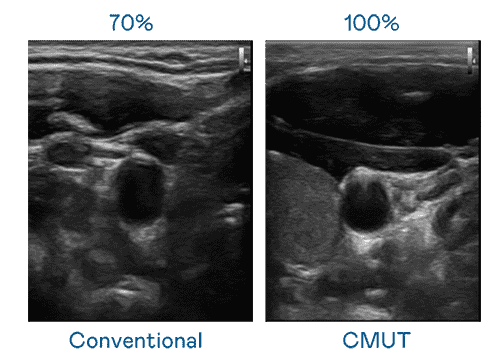

CMUT 技术是一种用电容式微机电元件来产生超音波讯号的技术。。。与传统 PZT 压电式技术相比,,CMUT 频宽增加 30%,,,,更宽频的超音波讯号让影像解析度大幅提升,,,是实现高影像品质医疗超音波扫描、、、、促进精准医疗发展的关键技术。。。。

大频宽带来超清晰影像

超音波影像的解析度高低,,首先取决于探头能发出的讯号频宽。。。优游UB8 CMUT 可提供高清晰的超音波讯号,,提供高频宽、、、高灵敏度、、、影像纹理细节更高的超音波影像,,,,协助医护人员缩短影像判读时间及利用精准的医疗影像进行诊断。。。